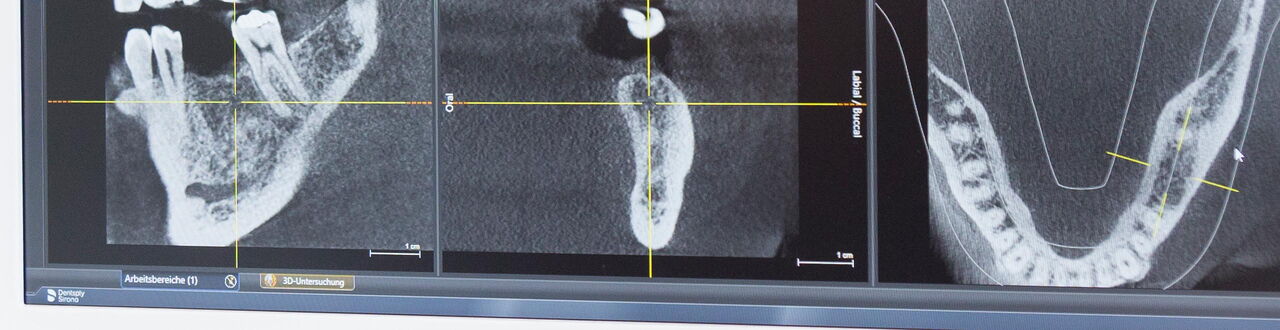

Zu unserem Leistungsspektrum gehört ebenfalls die Implantologie, also das Einsetzen von Implantaten im Ober- und Unterkiefer. Ein fehlender Zahn hinterlässt nicht nur optisch eine unschöne Lücke, sondern kann auch die Stabilität des gesamten Kiefers gefährden. Damit Sie weiterhin kraftvoll zubeißen können, wirken wir dem mit einem Implantat entgegen und erhalten auf diese Weise die Funktionalität der Knochensubstanz. Zahnimplantate stellen eine moderne Alternative zum herkömmlichen Zahnersatz dar. Als Implantat bezeichnet man eine künstliche Zahnwurzel, die fest im Kiefer verankert wird. Diese künstliche Zahnwurzel ähnelt einem schrauben- oder zylinderförmigen Dübel und bildet die Basis für Brücken, Kronen oder Prothesen. Nach dem Einbringen verwächst das Implantat mit dem umgebenen Knochengewebe und ist somit fest im Kiefer verankert.